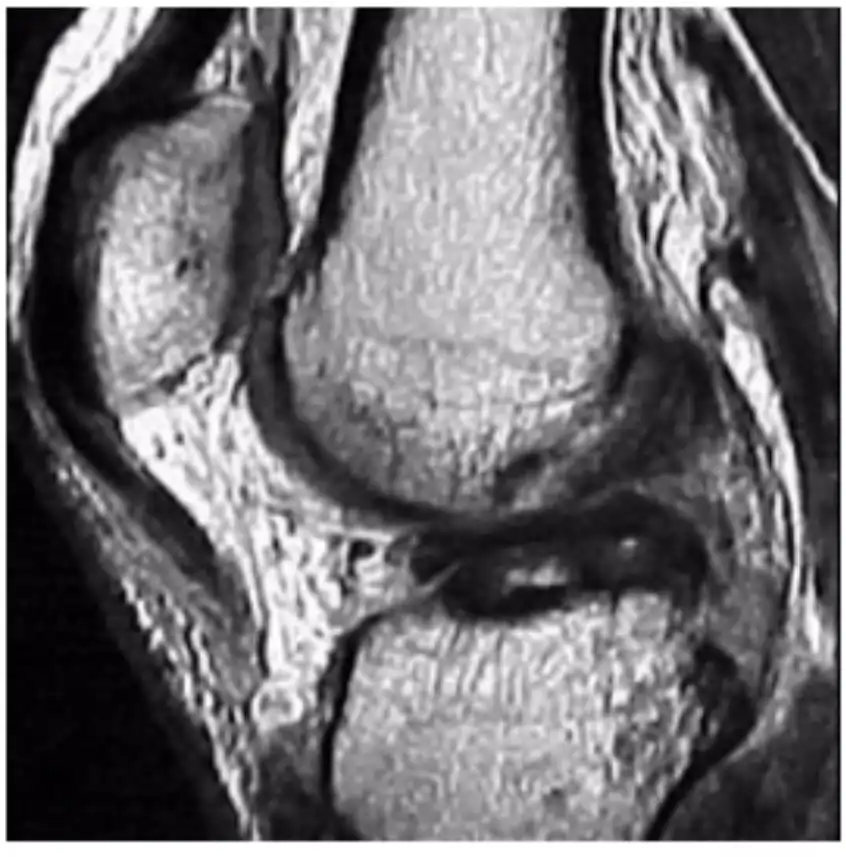

Lesões Meniscais do Joelho

Pacientes com lesões meniscais frequentemente sentem dor na linha articular, associada a bloqueio articular e sensação de instabilidade (falseio).

Tratamento

A vascularização do tecido meniscal é crucial para o planejamento do tratamento. Apenas o terço periférico do menisco é vascularizado, o que significa que lesões fora dessa área têm baixo potencial de cicatrização. A preservação do tecido meniscal é fundamental para manter o equilíbrio articular. Mesmo em lesões com baixo potencial de cicatrização que exigem meniscectomia (remoção meniscal), busca-se remover a menor quantidade possível de tecido.

- Pacientes submetidos à sutura meniscal devem evitar flexões maiores que 90 graus por 45 dias e são liberados para atividades esportivas após 6 meses da cirurgia.

- Pacientes submetidos à meniscectomia parcial são liberados para apoiar precoce e geralmente retornam às atividades físicas após 60 dias. É importante ressaltar que o tempo de recuperação pós-operatória varia e deve ser analisado caso a caso com o médico especialista.